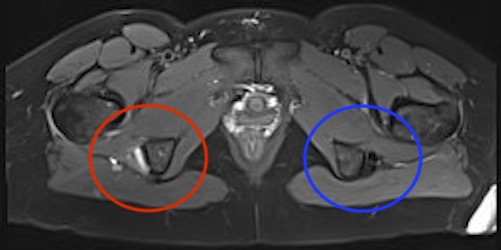

MRI

Proximal hamstring avulsion on right - red circle is retracted hamstring tendon, blue circle is normal insertion on left

Proximal hamstring tear on right (red circle), normal insertion on left (blue circle)